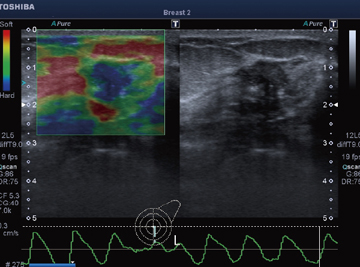

Realtime Application Platformとは,高速リアルタイム処理を実現し新アプリケーションを可能とするプラットフォームである。Elastographyをはじめ,びまん性肝疾患の評価に期待される当社独自のASQ(Acoustic Structure Quantification)をリアルタイム化(図4,5)。また,エコー像とCT像/MRI像を連動させ,病変の検出および治療支援に有効な"Smart Fusion"に対応している(図6)。このSmart Fusionは,通常のコンベックスプローブ以外にマイクロコンベックスプローブ,穿刺用コンベックスプローブにも対応しているため,早期発見から治療までを幅広くサポートする(図7)。また,磁気送信機は装置一体型のアームに取り付けるため,省スペースで移動も楽に行える(図8)。これらの機能により,病変の検出および質的診断に期待が持たれている。

![]() 図4 Elastography(乳腺腫瘍) |